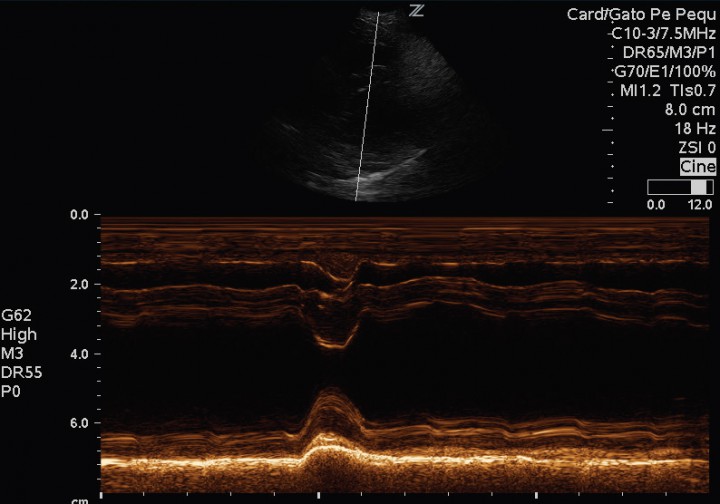

El paciente muestra disnea de tipo mixto y taquipnea (52 respiraciones por minuto). El estudio radiográfico del tórax revela la existencia de un patrón alveolar en zona perihiliar hacia lóbulos caudales compatible con edema pulmonar de tipo cardiogénico y un tamaño en el eje corte de 12 cuerpos vertebrales[ Buchanan JW, Bucheler J: Vertebral scale system to measure canine heart size in radiograms. J Am Vet Med Assoc 1995;206:194. [PubMed] ] (rango normal 9,7 +/- 0,3) (Fig. 2). Asimismo, el estudio ecocardiográfico muestra una sobrecarga de volumen ventricular izquierda, sin aumento del tamaño atrial, pero con dilatación de las venas pulmonares (Fig. 3). Las medidas ecocardiográficas muestran un aumento de la fracción de acortamiento (Fig. 4) y de eyección (VE), un ratio aorta aurícula izquierda correcto (Ratio ao/ai) y aumento del índice volumétrico telediastólico final (EDVI) (Tabla 1). No se observan alteraciones estructurales congénitas ni adquiridas.

<p>Modo M sobre músculos papilares en paraesternal derecho eje corto. Se observa una fracción de acortamiento mantenida, con espesores de septo interventricular y pared libre ventricular izquierda correctos.</p>

Figura 4

Modo M sobre músculos papilares en paraesternal derecho eje corto. Se observa una fracción de acortamiento mantenida, con espesores de septo interventricular y pared libre ventricular izquierda correctos.